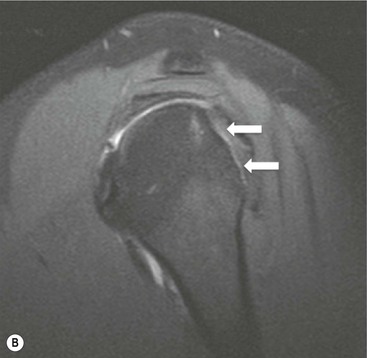

The primary sign of a rotator cuff FTT is a focal deficiency of the tendon (Figs. 46-4 and 46-5). This nearly always occurs at the tendon insertion on the tuberosity. The margins of the tear are best delineated when there is fluid within the tendon defect. Secondary signs of an FTT include the presence of fluid in both the GHJ and SAB, and flattening or concavity of the subacromial fat plane.

PTTs are less reliably demonstrated by both MRI and US, and it may be difficult to differentiate tendinopathy from partial tears. Focal clefts, tears, or tendon thinning affecting the articular margin of the footprint of the tuberosity are most common (Figs. 46-6 and 46-7). Tendon thickening is not always present. It is important not to mistake magic angle phenomenon on short TE MR sequences or anisotropy on US as evidence of tendinopathy.2